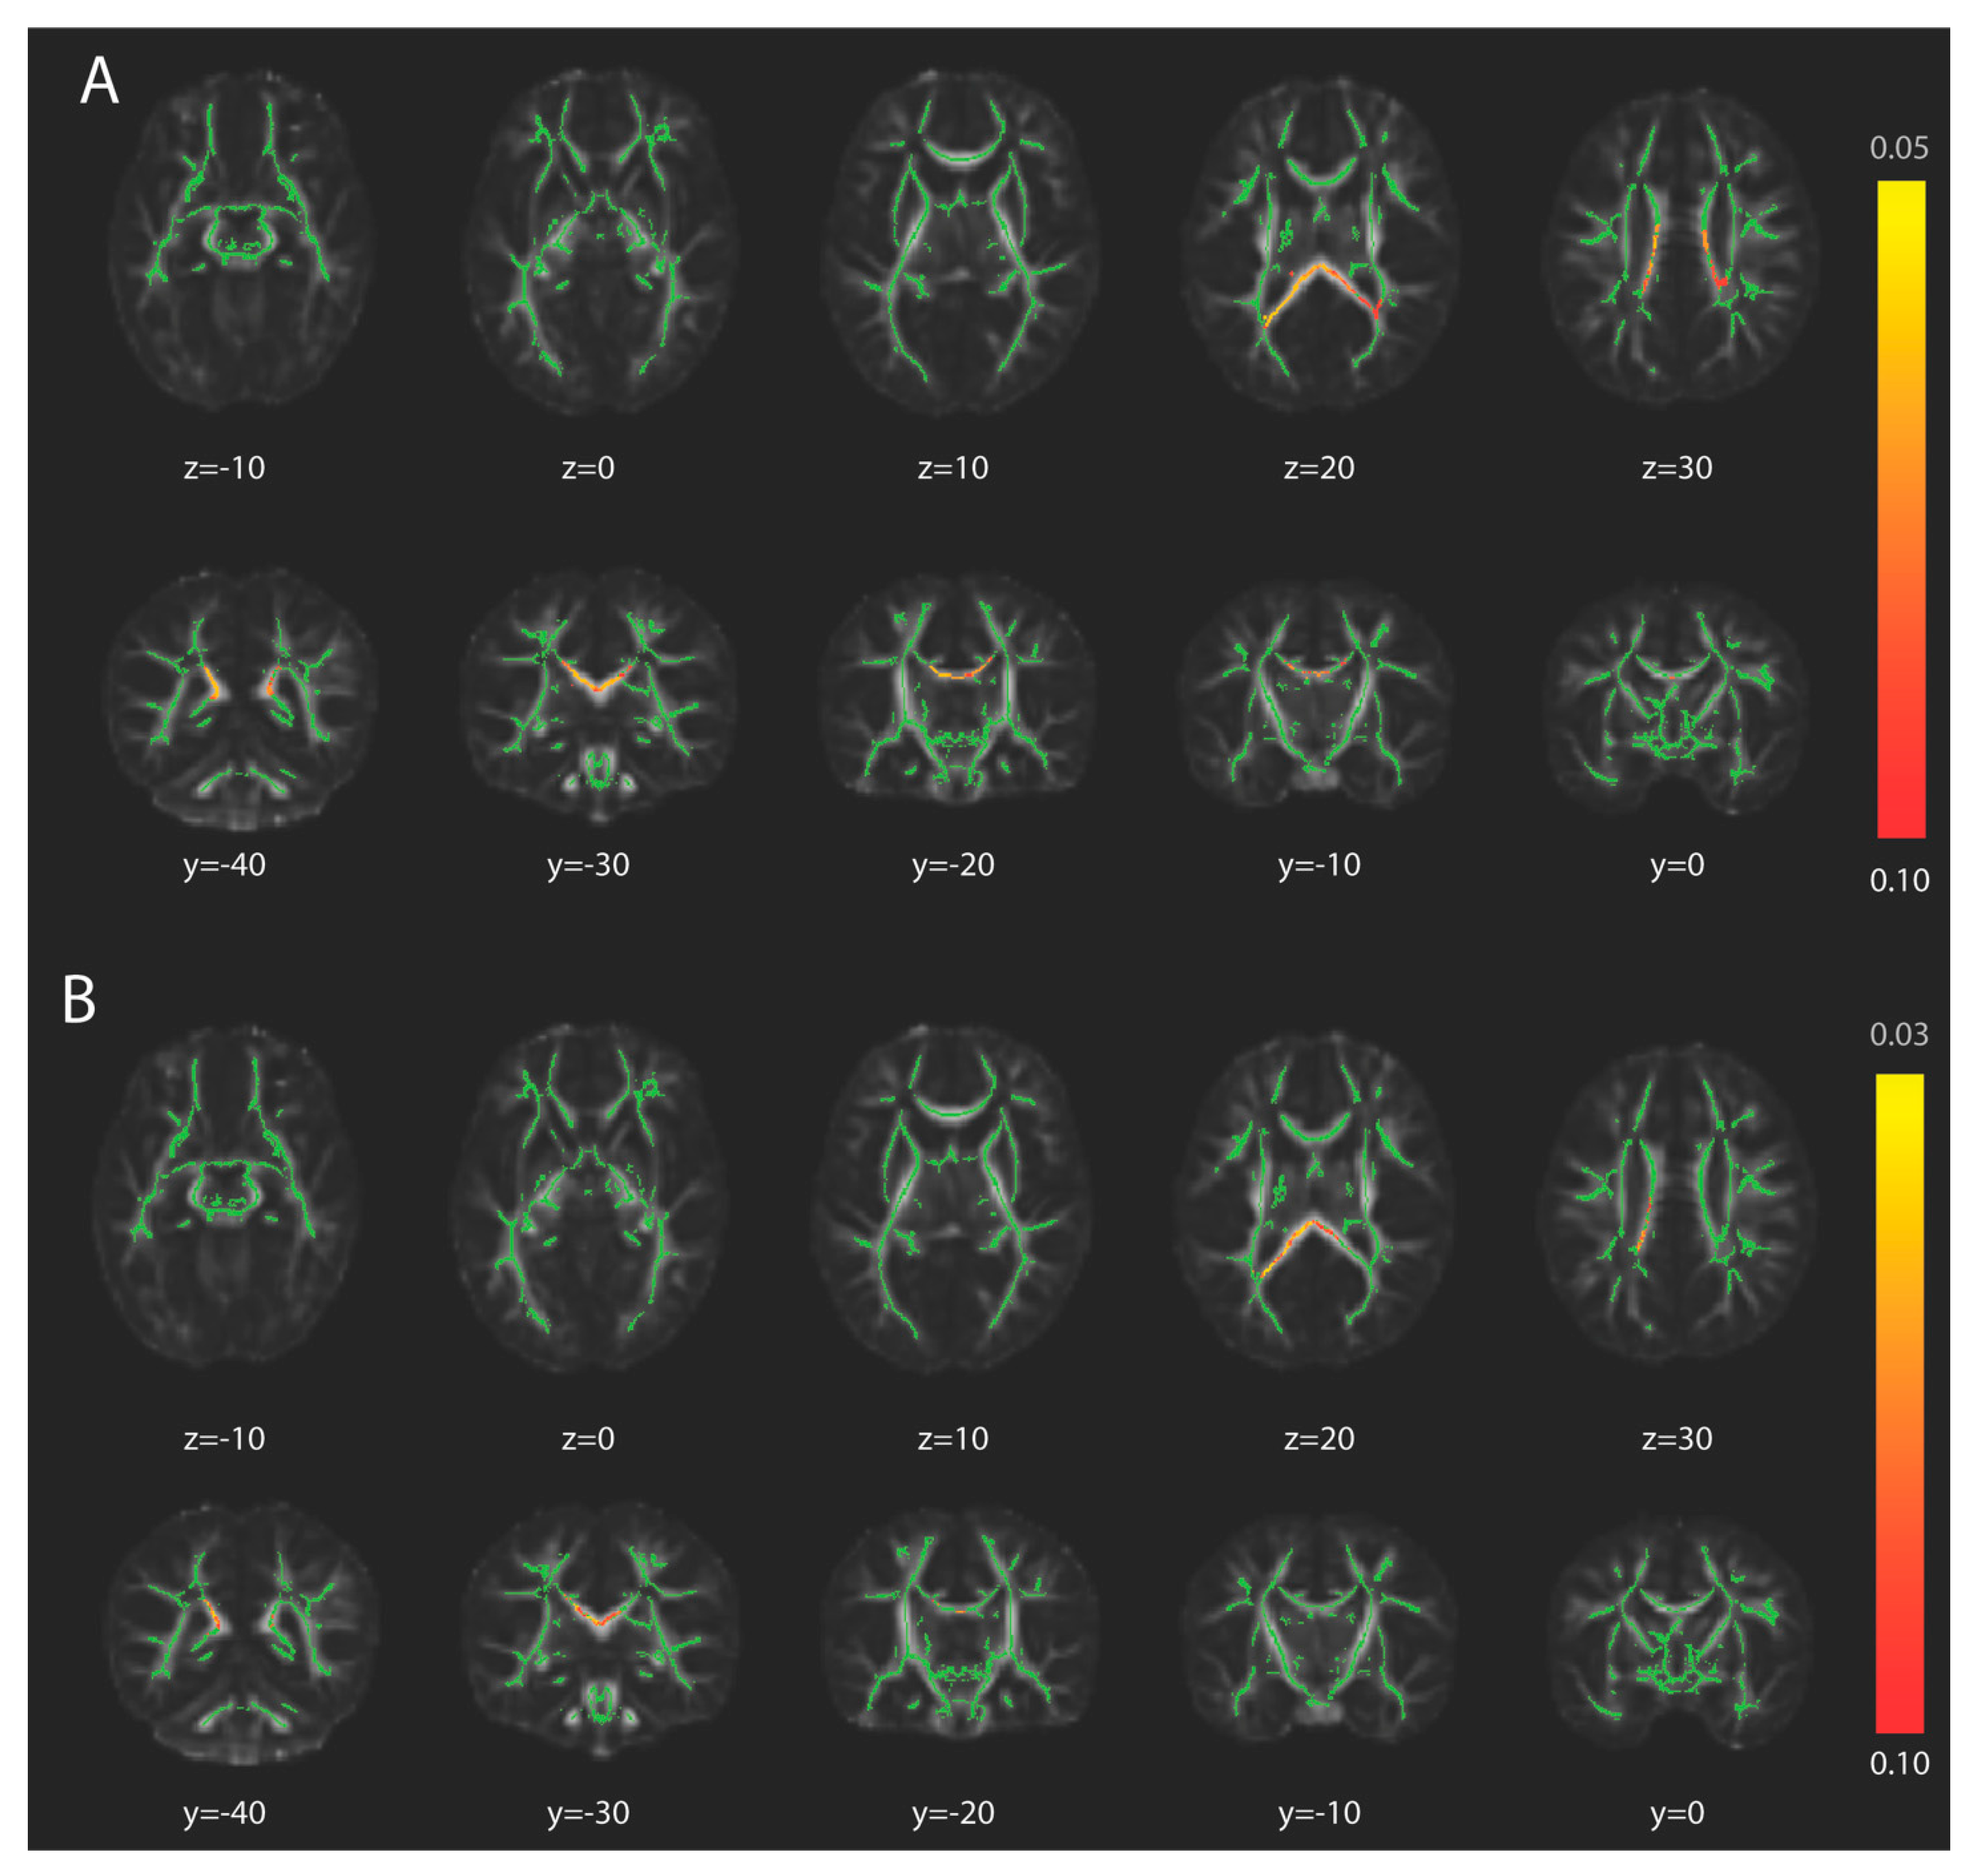

3.2. Tract-Based Spatial Statistics

2.4.3. TBSS

2.5.2. TBSS